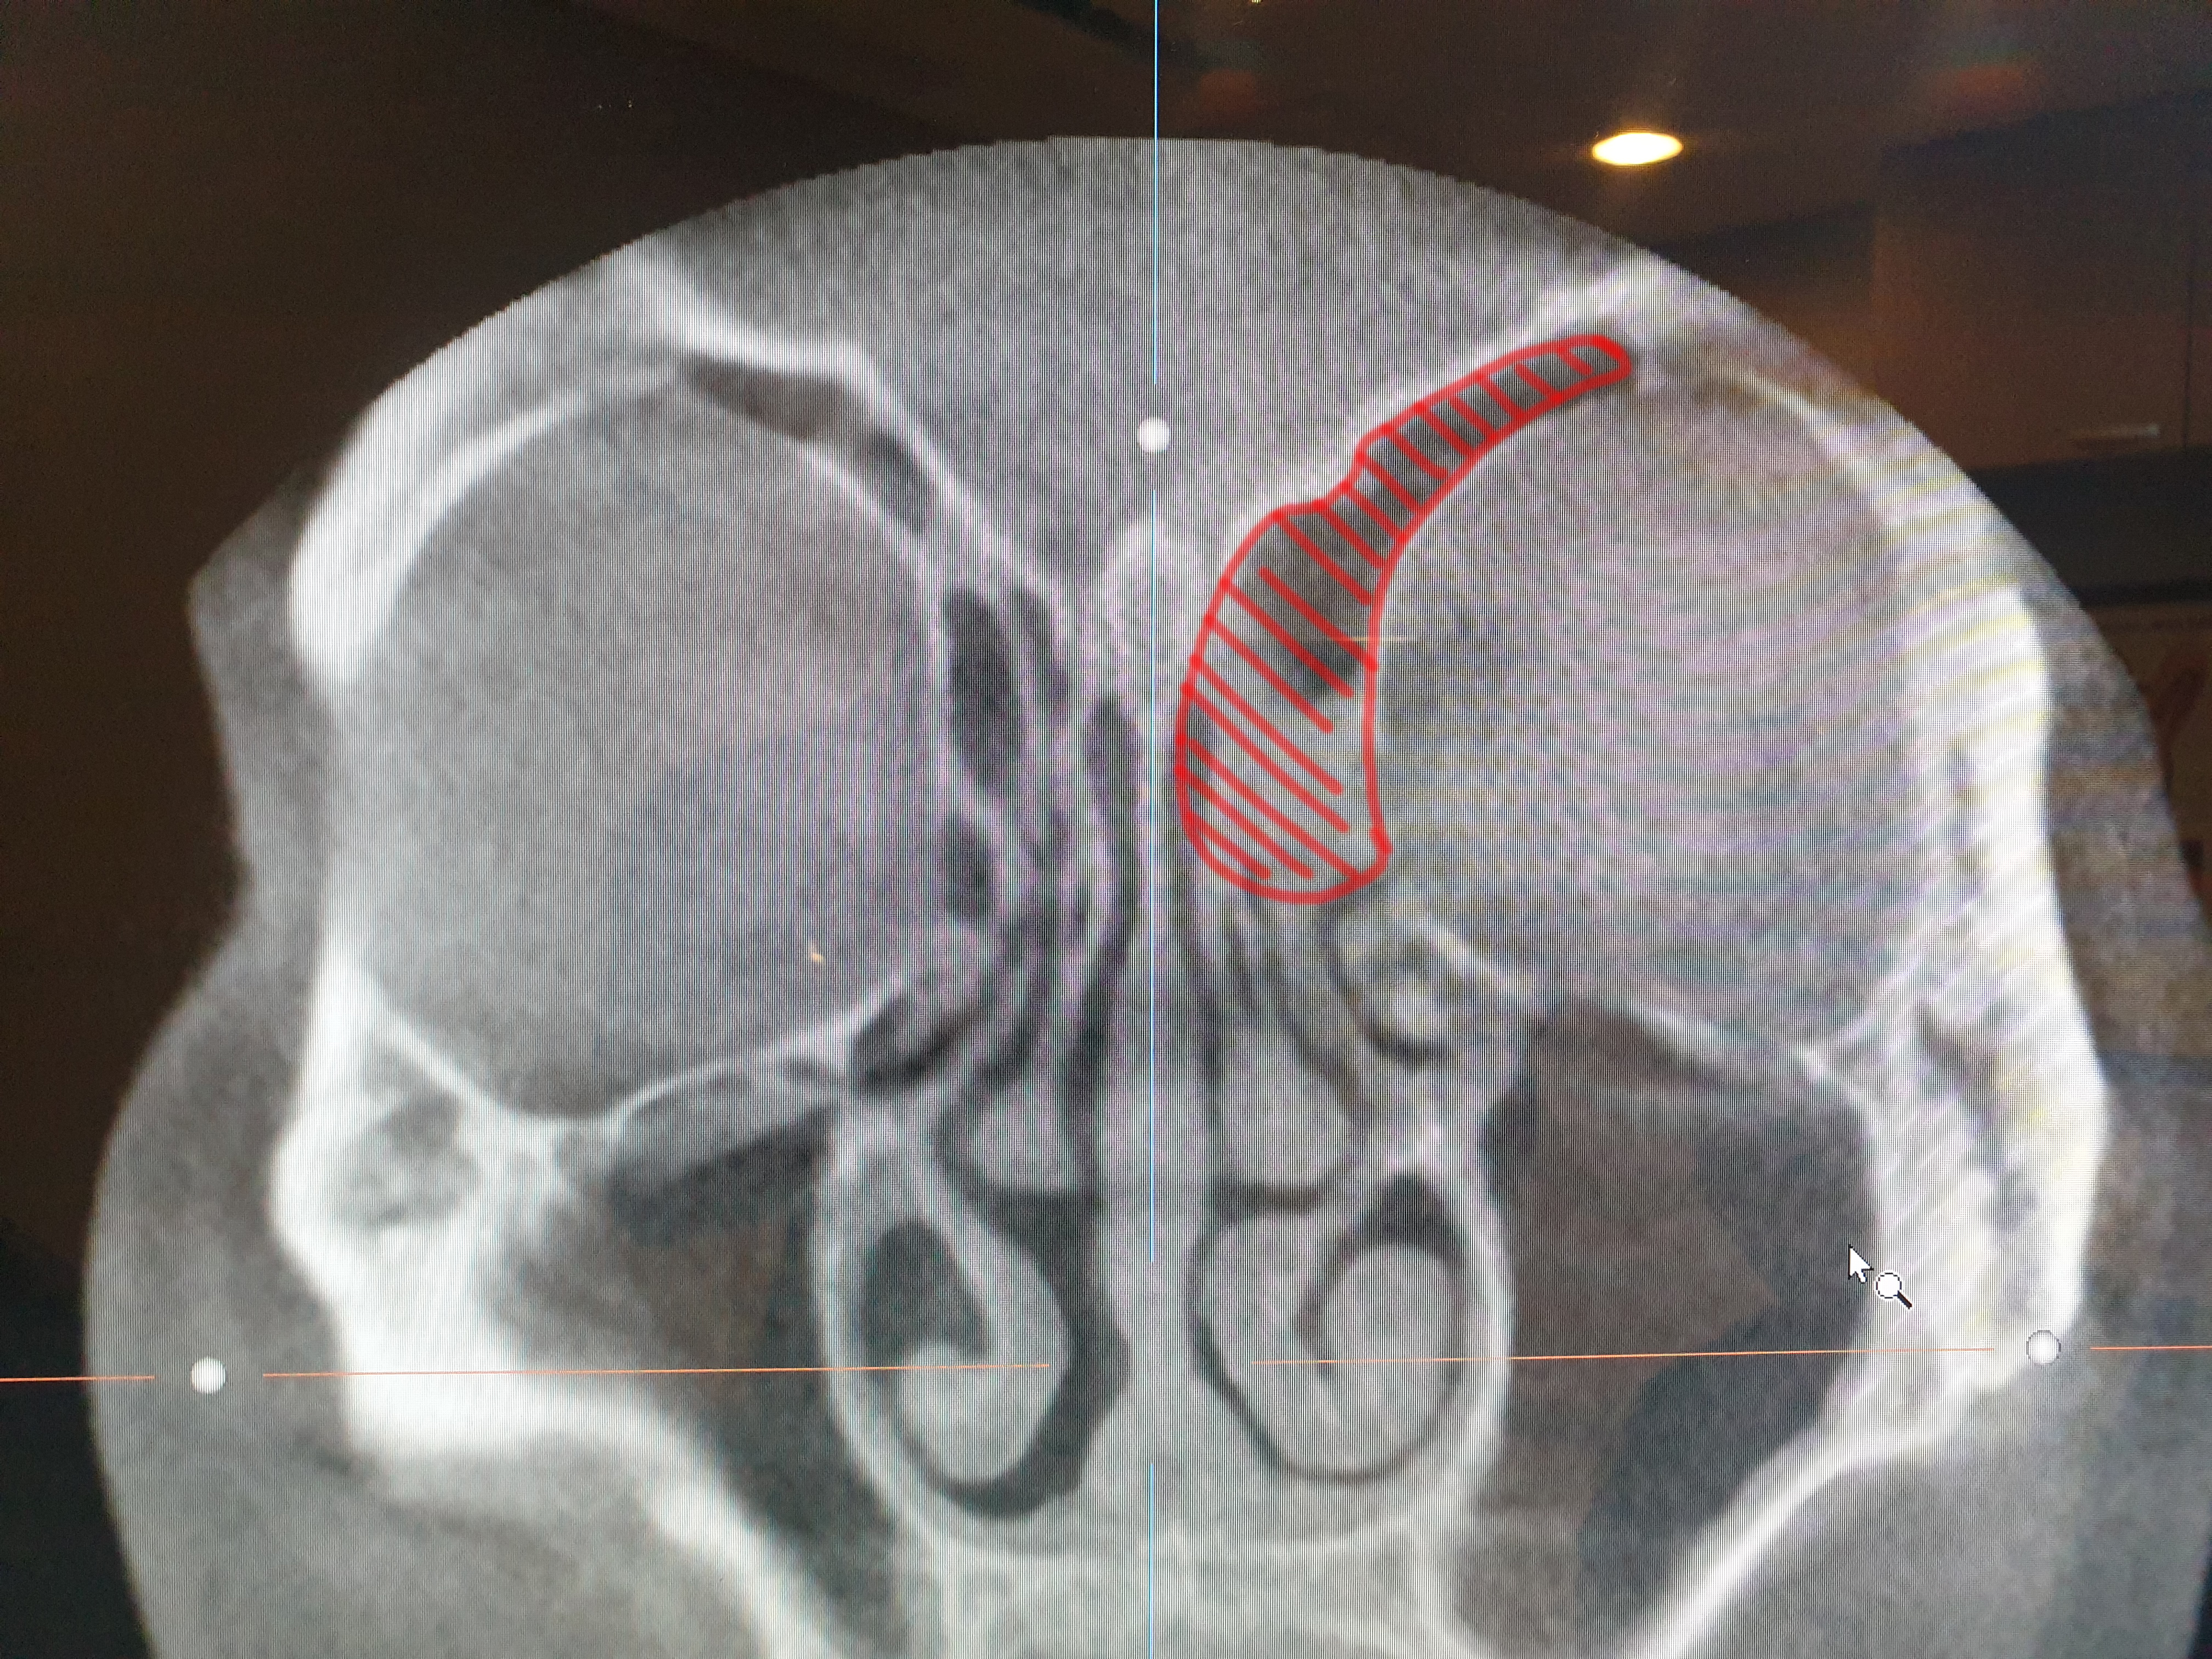

그래도 다행인 거는

심한 경우 위 사진처럼 붉은색 영역까지 농이 차는 경우도

있다고 하셨다. 아마도 이게 축농증이지 않을까?